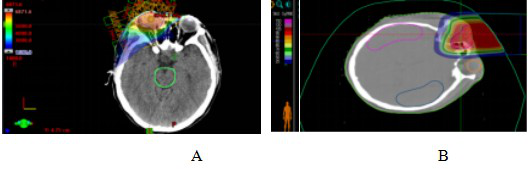

Case 2: Male, 38 years old, malignant melanoma of the choroid of the right eye. He presented to our hospital in April 2023 with a funduscopic examination that showed a clear and reddish optic disc border, a brownish-black highly elevated mass visible in the temporal inferior quadrant of the retina, and secondary retinal detachment in the periphery of the mass, which was spreading to the macular area. The patient was treated with CIRT from 25 April to 12 May 2023 after a thorough examination and evaluation. The prescribed dose was PTV 70Gy/14Fx, 5GyE/Fx. Supine position, 2D uniform scanning technique, dose distribution is shown in Fig. 4. Typical comparison of dose distribution in axial images between CIRT and VMAT plans while both fulfilling the prescription requirements, peripheral normal tissues were significantly reduced in the range of low-dose irradiation for the CIRT plan compared to the VMAT plan, as shown in Fig. 5. During the treatment period the patient was given Teraplizumab injection (240 mg) for 2 cycles of immunotherapy.The efficacy of CIRT was compared by imaging data before and after treatment, and the patient's efficacy was assessed according to the RECIST1.1 criteria for evaluating oncological efficacy, and the efficacy of the treatment was a CR at 3 months post-treatment, as shown in Fig. 6.During the period of CIRT treatment and 1 month post-treatment, the patient experienced grade 1 radioskin lesions, with the same visual acuity as before, and no greater than grade 2 adverse events, and visual acuity improved 3 months after treatment. As of September 2024, the patient is currently disease-free and continues to be followed up on a long-term basis.

Figure 4 CIRT dose distribution in patients with malignant choroidal melanoma

Figure 5 VMAT plan and carbon ion plan dose distribution in patients with malignant choroidal melanoma

Note: Figure 5A: VMAT plan dose distribution in patients with malignant choroidal melanoma. Figure 5B: Carbon ion plan dose distribution in patients with malignant choroidal melanoma.